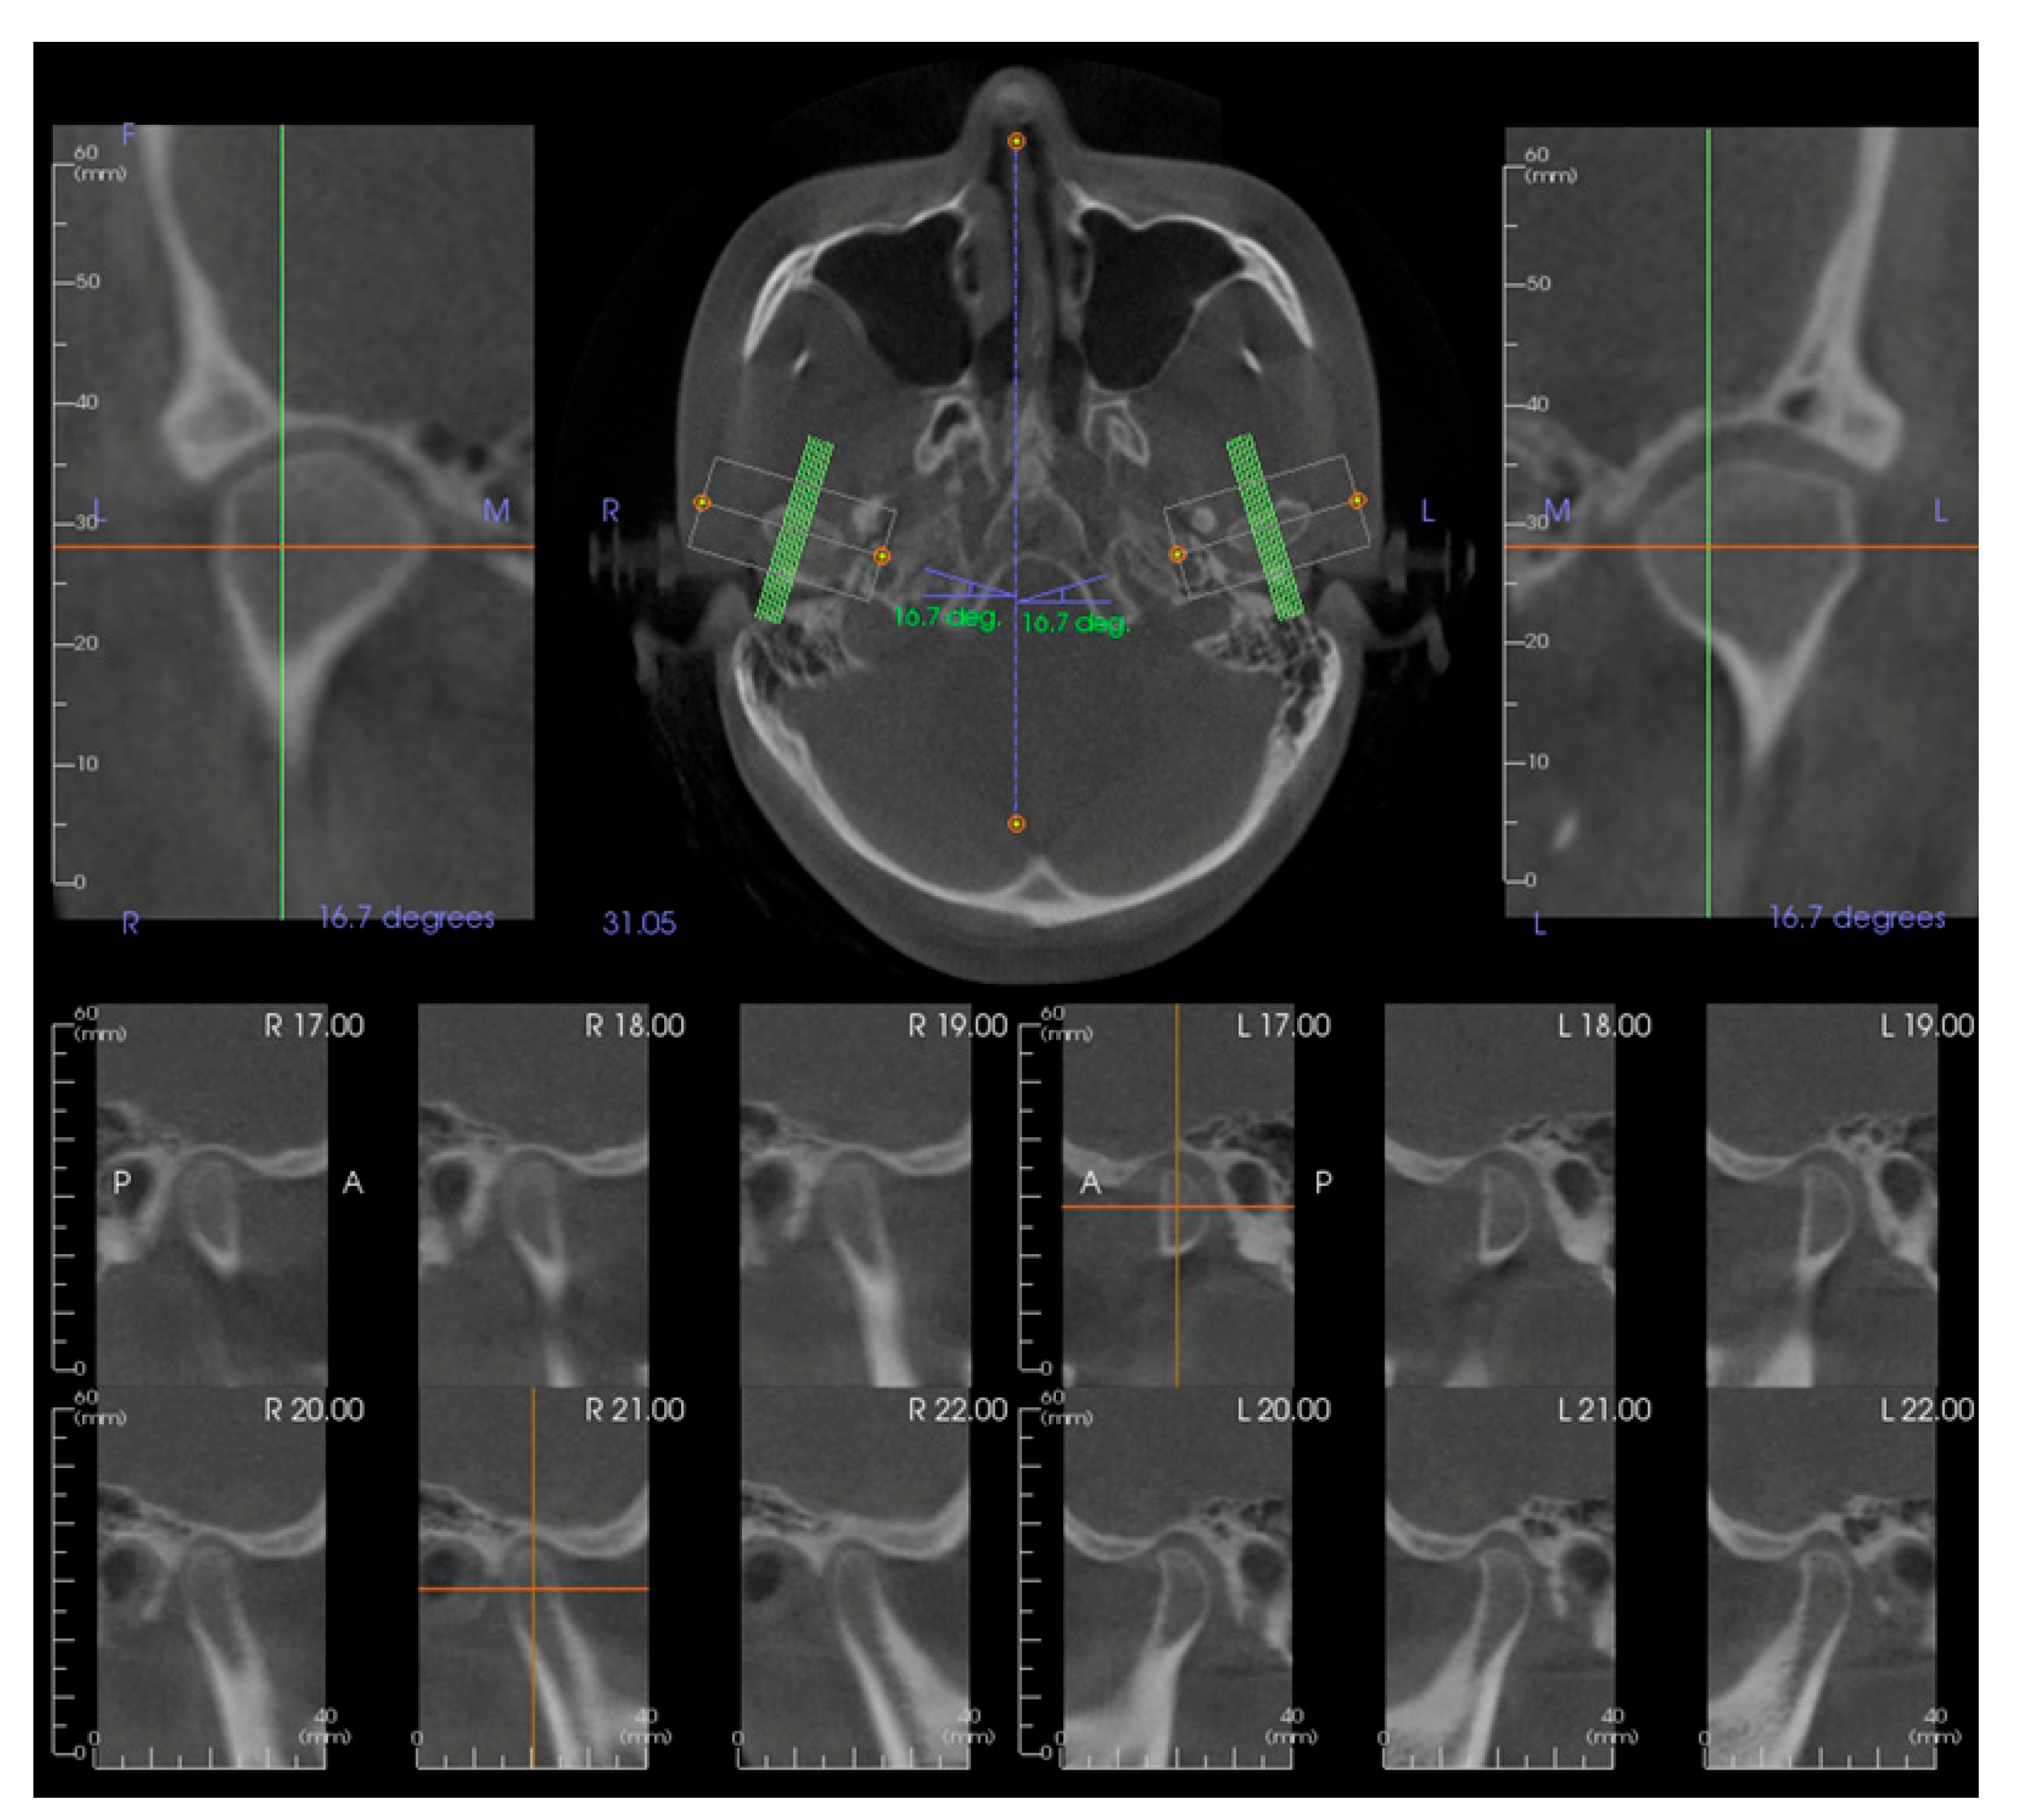

2.2. Subjects, Eligibility Criteria, and Cone-Beam Computed Tomography (CBCT)

2.3. Study Design